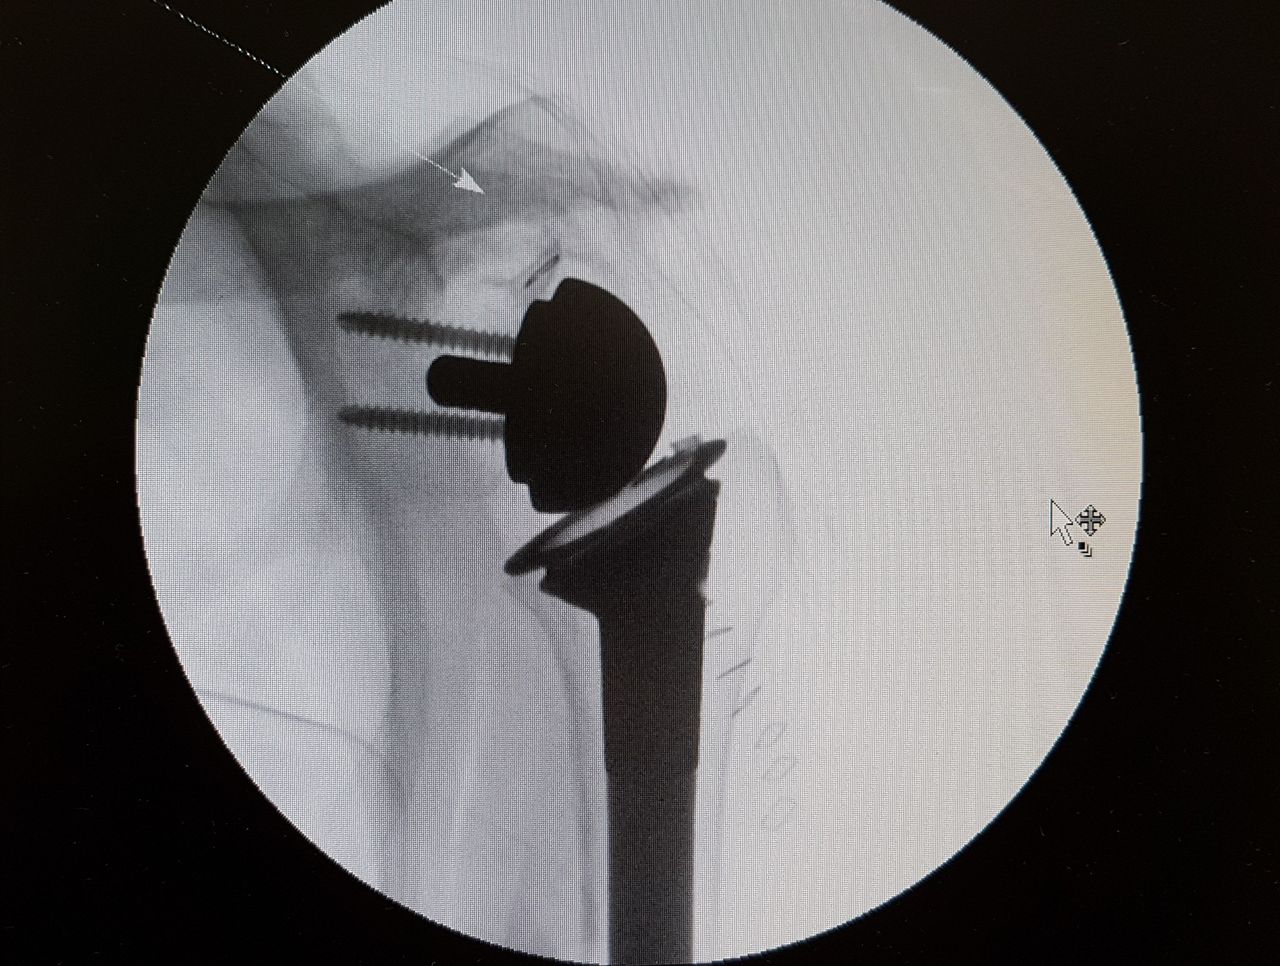

Specialista di chirurgia della Spalla, del Gomito e di traumatologia dello sport. Opinion leader e docente di fama Europea della patologia dell'arto superiore, con particolare interesse verso le ricostruzioni legamentose, l'artroscopia, la sostituzione protesica ed interventi di revisione. Gran parte della mia pratica clinica e chirurgica è attualmente il trattamento di fallimenti di altri interventi o traumi non guariti correttamente e il trattamento dell'atleta ad alto livello con patologie di spalla e gomito.

Parallelamente all'attività chirurgica di revisione ho da sempre approfondito la chirurgia mini invasiva dell'arto superiore, soprattutto sviluppando techniche chirurgiche come l'artroscopia di gomito e la fissazione esterna per le fratture di omero prossimale.

Most of my surgical practice is currently the treatment of failures of prior surgeries and post traumatic deformities. I'm also greatly involved in the treatment of high level athletes and I developed my skills in mini-invasive surgeries, especially elbow arthroscopy and mini-invasive techniques for the treatment of proximal humeral fractures.